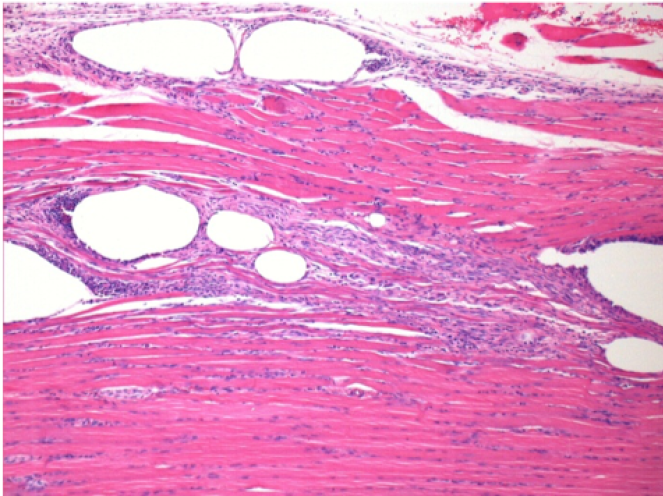

بعد شهر من حقن إندوبيل

بعد شهر واحد من حقن Endopeel 0.1 مل في العضلة أمام الظنبوب اليمنى.

ما يظهر باللون الأسود في الصور ليس نخرًا كما يتصور بعض العلماء!

في الواقع ، يجب أخذ 4 استنتاجات في الاعتبار :

- قطعة أثرية من التلوين

- عدم وجود نخر

- عملية بيولوجية

- موت الخلايا المبرمج

L : Control-100xD30

R:100xD30

R :400xD30